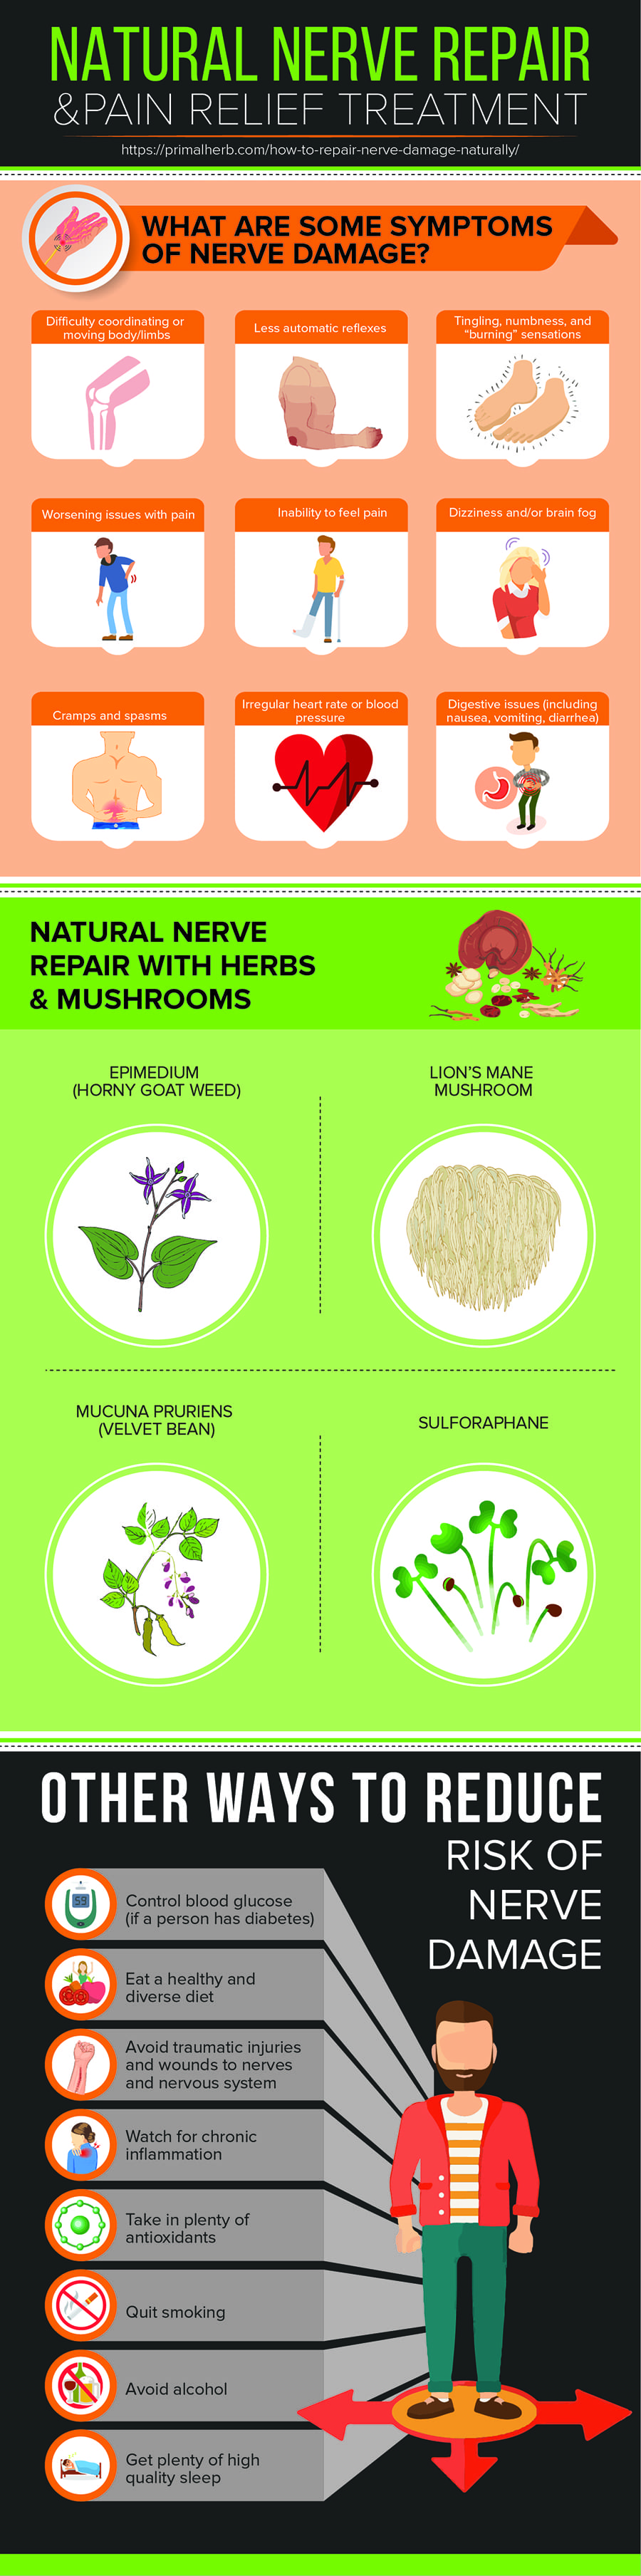

Ct or mri scans can look for herniated disks, pinched nerves, also called compressed nerves, growths or other problems affecting the blood vessels and bones. Boeing tries to build a ‘neutral’ nerve center the structural weaknesses in boeing’s planemaking flow can actually be quite neatly traced to strategic missteps that. Current therapies to repair nerve damage involve transplanting the patients' healthy nerves to repair damage or implanting an artificial nerve guidance conduit.

5 min read your nervous system is involved in everything your body does, from regulating your breathing to controlling your. Find out how to prepare for. Peripheral nerve injuries are one of the most common causes of hand dysfunction caused by upper limb trauma but still current management has.

Peripheral neuropathy happens when the nerves that are located outside of the brain and spinal cord (peripheral nerves) are damaged. Having a ct scan might involve having a. Chemotherapy certain medications certain types of infections nutrient deficiencies (especially vitamins) these are certainly not all the possible causes.